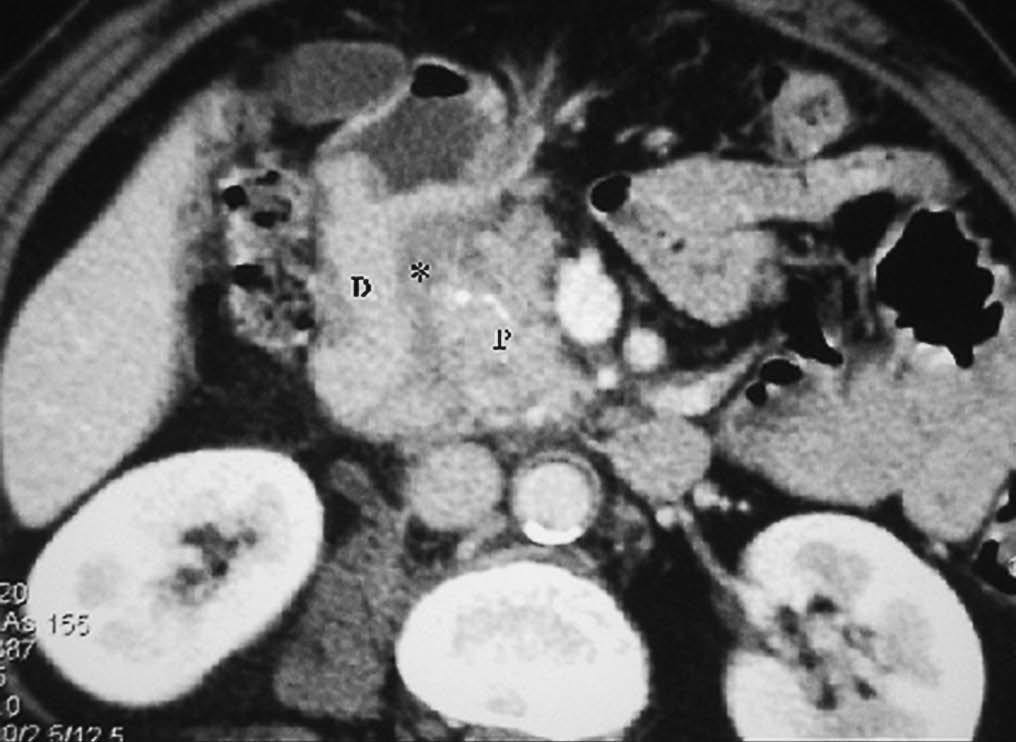

El duodeno es una localización infrecuente de diverticulitis. La imagen radiológica consiste en un engrosamiento de la pared del duodeno asociado a un divertículo, en ocasiones con un enterolito en su interior, con inflamación de la grasa adyacente16 (fig. 9).

Fig. 9--Diverticulitis duodenal. (A) En la ecografía se observa un divertículo (flechas) con engrosamiento de pared duodenal (D) y alteración de la grasa adyacente (*). (B) Tomografía computarizada de otro paciente con inflamación de divertículo duodenal. Se oberva una lesión quística (punta de flecha) de pared gruesa y borrosa, con material en su interior. P: Páncreas.